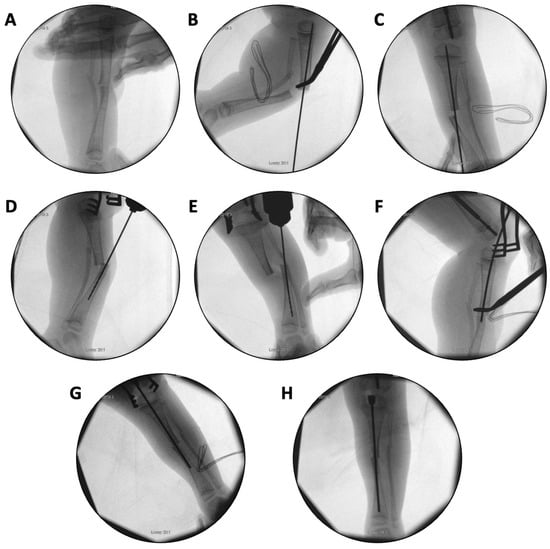

In the first case, a three-year-old skeletally immature girl diagnosed with OI type III presented for surgical correction of significant right tibial bowing using a SLIM nail. After identifying the CORA (Figure 8), an anterior opening-wedge osteotomy was performed at the midshaft of the right tibia to realign the bone (Figure 9A). The proximal canal was sequentially reamed from the osteotomy site to accommodate the SLIM nail, and a medial parapatellar approach was used to retrieve the reamer at the level of the knee (Figure 9B,C). The distal tibia was similarly reamed up to the distal physis (Figure 9D,E). The SLIM nail was inserted through the knee and positioned centrally within the canal with good bony contact on all sides, with the proximal threading positioned in the epiphysis (Figure 9F–H). Fluoroscopy confirmed excellent alignment, and no additional internal fixation was needed. In this case, the indication for using a SLIM nail was the narrow intramedullary canal of the tibia in a skeletally immature patient requiring deformity correction. A larger nail could not be used due to anatomical limitations, making the SLIM nail the appropriate choice.

Figure 9.

(A–H): Series of intraoperative fluoroscopy images demonstrating insertion of the SLIM nail. (A) After osteotomy, the fracture is reduced. (B) Lateral view of proximal reaming through the osteotomy site. (C) AP view of proximal reaming through the osteotomy site. (D) Lateral view of distal reaming through the osteotomy site. (E) AP view distal reaming through the osteotomy site. (F) Insertion of the SLIM nail. (G) SLIM nail is gradually advanced past the osteotomy site. (H) AP view of installed SLIM nail, with proximal threading in the epiphysis.